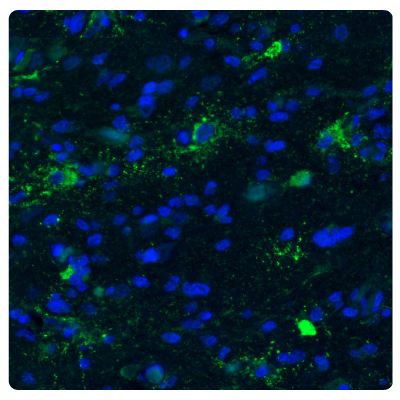

An example is ChI3L1 as a modulator of stem cell cellular states. Phenotypic plasticity in human tumors can be driven by activation of the epithelial-to-mesenchymal transition (EMT) process by which cells acquire plasticity and gain the properties of stem cells. CHI3L1 is a secreted protein acting as a modulator of stem cell states and is highly expressed in gliomas. CHI3L1 is used as a marker for invasion, migration, and angiogenesis in glioblastoma.16 Figure 4 shows an example of immunostaining astrocytoma with an Anti-CHI3L1 antibody.

Figure 4A.Fluorescence immunohistochemistry images of human normal cortex tissue samples stained with the Anti-CHI3L1 antibody. Nuclei are counterstained by DAPI (in blue).

Figure 4B.Fluorescence immunohistochemistry images of astrocytoma samples stained with the Anti-CHI3L1 antibody showing strong protein expression (in green). Nuclei are counterstained by DAPI (in blue).